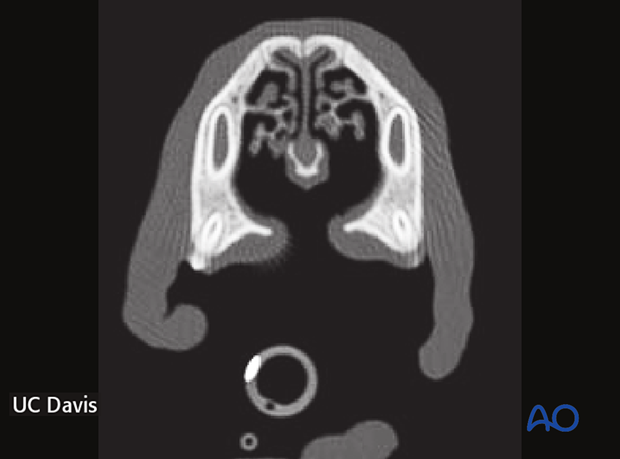

In assessing patients for a palatal surgery, the defect's size and shape are evaluated under general anesthesia. CT imaging is recommended, and dental extractions, if needed, are done before cleft repair.

A CP defect is a clinical diagnosis facilitated by radiographs, including occlusal intraoral radiograph and two (left and right rostral maxilla) lateral intraoral views obtained by a bisecting angle technique.

A CT and a 3D reconstruction are indicated to evaluate better the relationship between soft and hard tissues and to diagnose any coexisting craniofacial abnormalities. The osseous defect is larger than the overlying soft tissue defect.